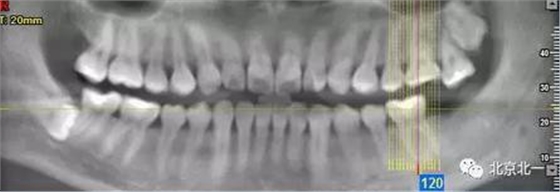

病例資料:一般情況,患者女性,28歲, 主訴:要求拔右側(cè)下頜智齒,檢查:右側(cè)下頜第三磨牙未見(jiàn)萌出, 拍片如圖。

圖一:CBCT顯示右側(cè)下頜水平骨埋伏牙,牙冠距離下牙槽神經(jīng)管接近。

圖二:自帶的CBCT顯示下牙槽神經(jīng)管貼著智齒走形。